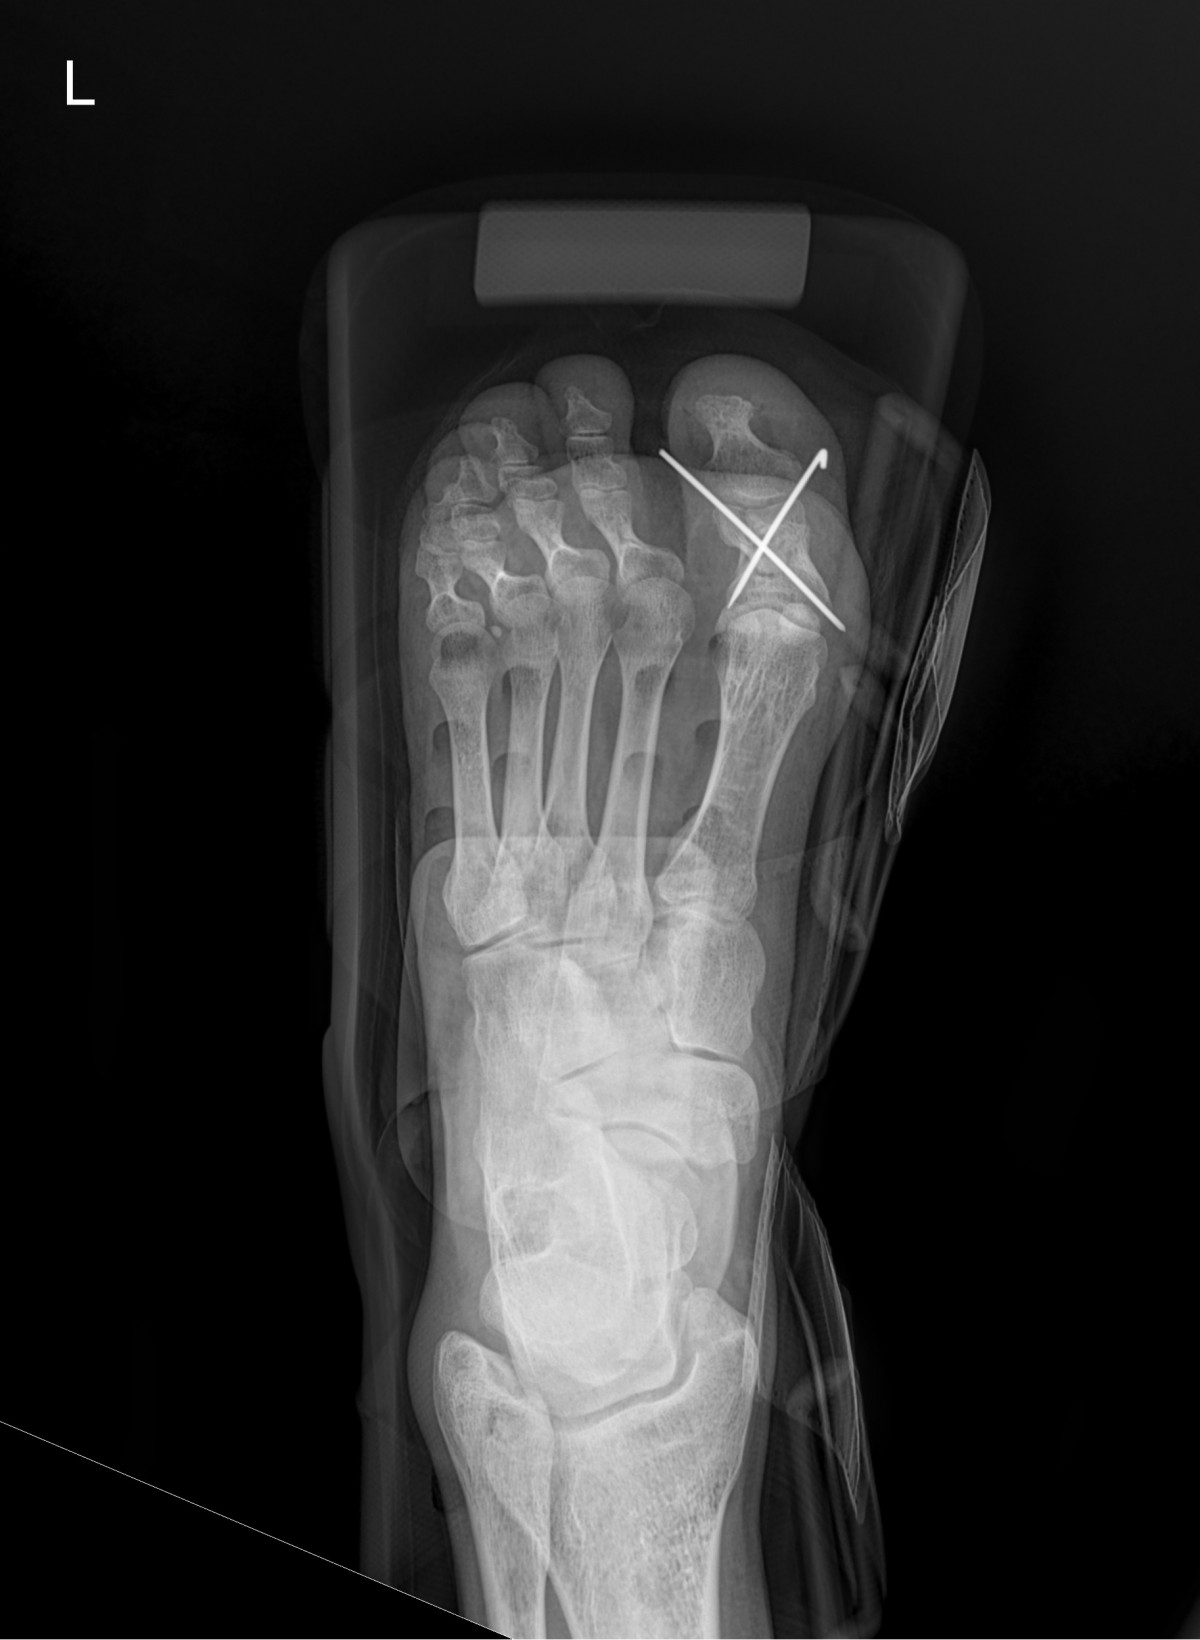

정지영원장님 발가락 골절 수술 강완O 환자

dae765e4d9ac96aee867c9d6292d8784_1758008768_4388.jpg